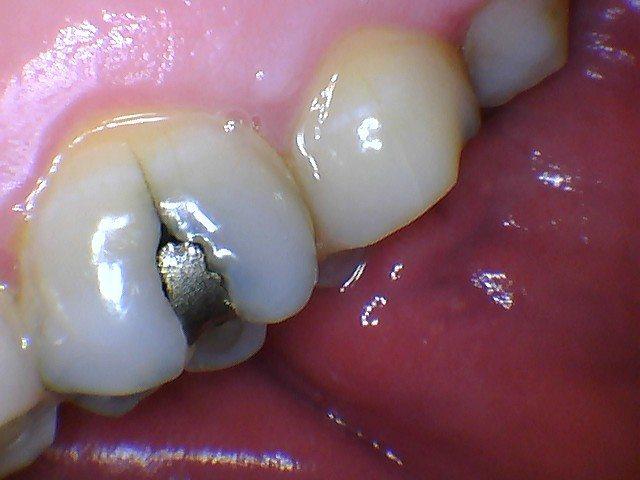

Intraoral Camera

Intraoral cameras are used to help educate patients about their oral health. With the use of a camera patients are able to see the condition of their mouth. Photos aid us in discussing disease and how it can be prevented

.